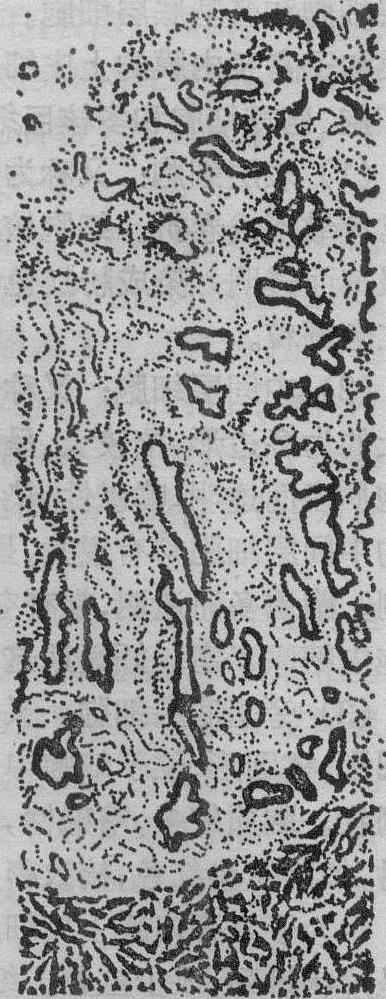

增生早期 又称经后期或修复期,约在月经周期第5~7天。内膜厚约1~2mm,腺体短直而稀少(图1)。腺上皮细胞和表面上皮细胞呈低柱状或立方状。细胞质含有许多核糖体,线粒体散在胞质中。核卵圆形,大而深染。细胞增生活跃。细胞顶部含有少量碱性磷酸酶(AlP)和酸性磷酸酶(AcP)。内膜间质致密,基质细胞呈梭形,核大着色深,胞质少。螺旋动脉较直,壁薄,内皮细胞含有少量AlP。

图1 子宫内膜增生早期(月经周期第5天)